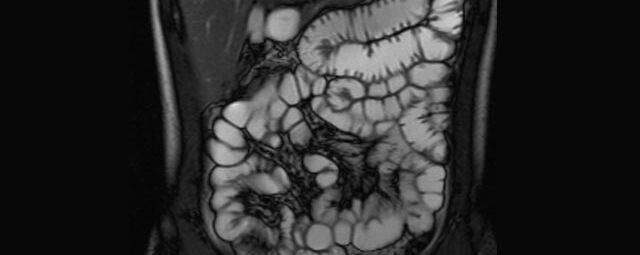

Abdomen/Becken

• Darm

• Darstellung bzw. Kontrolle im Verlauf bei perianalen Fisteln und Abszessen

• Verlaufskontrolle des Lokalbefundes nach Rektumentfernung bei Karzinom